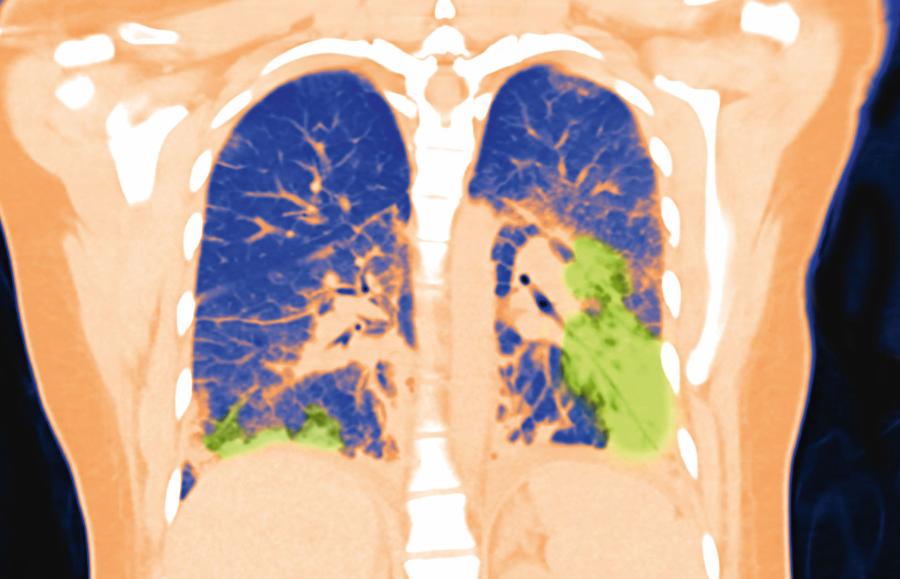

Zniszczone płuca 19-­latki – efekt choroby EVALI, spowodowanej używaniem nielegalnych liquidów do e-papierosówBE&W Zniszczone płuca 19-­latki – efekt choroby EVALI, spowodowanej używaniem nielegalnych liquidów do e-papierosów